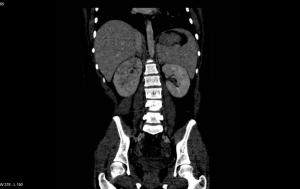

Image IQ Quiz: Patient Presents with Fever and Abdominal Pain

March 23rd 2021

What is your diagnosis in this case with a patient presenting with a fever and abdominal pain?

• Image IQ Quiz: Patient Presents with Fever and Abdominal Pain

Published: March 23rd 2021 | Updated: